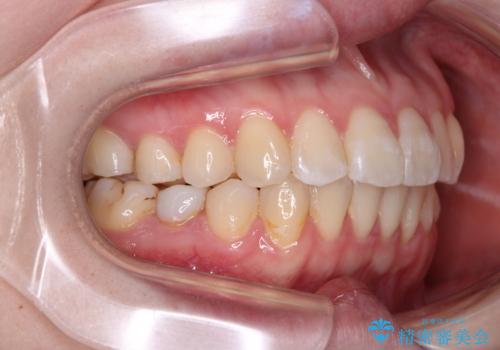

開咬と前方に飛び出した前歯 インビザラインによる矯正治療

- 上下前歯の非接触と叢生を気にして来院された患者様です。

開咬の改善はインビザラインの最も得意とするところであるため、インビザラインを用いて矯正治療を行うこととしました。

舌の突出癖改善のトレーニングをしっかりと行っていただき、上下前歯が接触する咬み合わせを達成することができました。